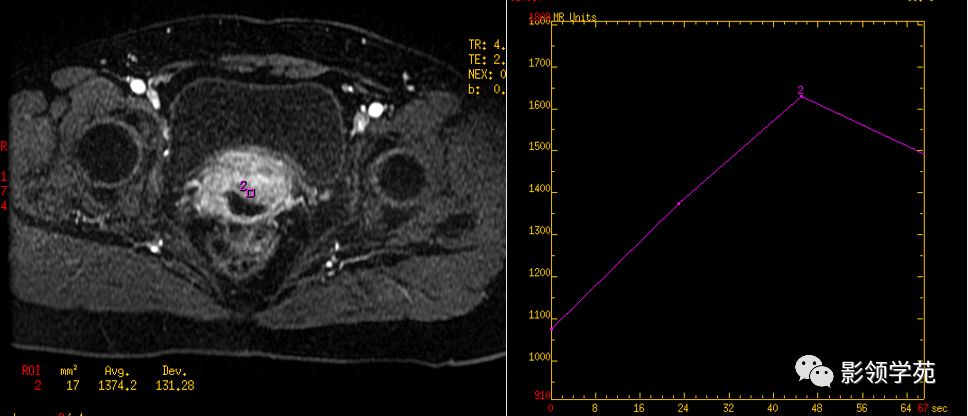

磁共振动态增强在宫颈癌中的应用

DCE-MRI是一种无创性功能成像方法,利用静脉注射对比剂的同时行连续多层扫描,以获得组织或肿瘤增强的时间-信号曲线(TDC),直接从毛细血管水平反映肿瘤内血流动力学变化,获得肿瘤灌注和毛细血管通透性等参数。

动态增强时间信号曲线

- 恶性肿瘤的动态增强模式多数为早期快速强化后缓慢减低或早期强化后持续强化出现“平台期”;

- 良性肿瘤或正常组织多表现为缓慢持续强化或无强化。

- 对宫颈癌的动态增强研究显示为“速升缓降型,或速升速降型”,动脉早期即明显强化,强化程度高于子宫肌层及宫颈基质,其达峰时间为注射造影剂后30~60 S。静脉期及延迟期逐渐廓清,至延迟期信号强度低于周围基质。